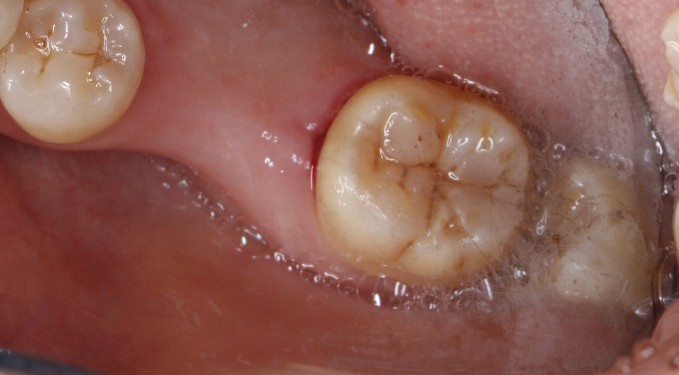

绝大多数人的智齿还是应该及早拔掉,在国外一般十几岁的少年就把智齿预防性拔除。因为智齿是最后萌出的牙,长出来时,牙床往往已经没有"立足之地了",往往长得歪斜,且不能萌出至正常位置。这会影响周围牙龈软组织和相邻牙齿,引发周围牙龈软组织红肿、炎症、疼痛,导致冠周炎和严重的口腔颌面部感染,甚至有可能成为关节痛和不明原因神经痛的诱因。